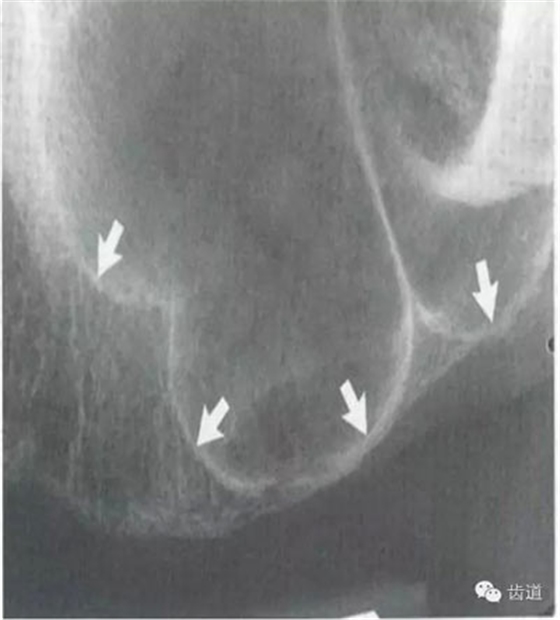

6)下頜骨下緣:

膠片在口內(nèi)放的位置過(guò)低,在牙根尖下方X線片上顯示為帶狀密度很高的影像。

7)下頜角區(qū):

在下頜管的后下區(qū)域,骨小梁稀少,這是正常骨質(zhì)疏松區(qū)域 8)頦嵴:

在正中聯(lián)合的兩旁,各有一致密影像帶,呈八字形延長(zhǎng)至前磨牙區(qū),是頦嵴的影像。